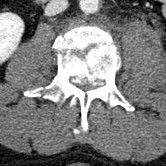

The fly-through doesn’t show the spinal injury very well, so here are some 2-D sections. The left panel is a section of my lumbar spine viewed from my left side; note the obviously smashed L3 vertebra. The middle panel is a top-view slide of L3, and the right panel is healthy L2 (the vertebra immediately above) for comparison.